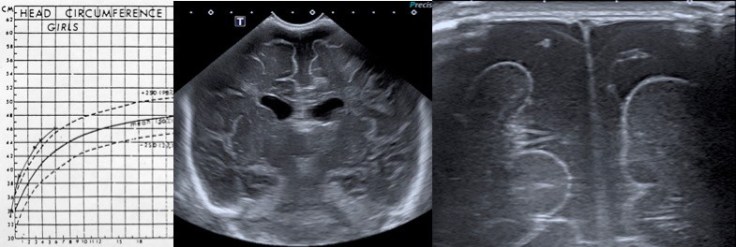

la macrocéphalie apparaît entre 3 et 6 mois, chez un enfant présentant souvent déjà à la naissance un PC dans les valeurs normales hautes ; le PC augmente de façon régulière, sans cassure de la courbe. l’enfant présente un bon développement, mais parfois un retard d’acquisition du tonus axial peut être présent :

il existe souvent une prédisposition familiale, et on retrouve régulièrement un PC élevé chez un des parents.

- l’échographie montre que le liquide est situé dans l’espace sous-arachnoïdien et non sous-dural, sachant que les deux peuvent co-exister. la valeur limite de la distance sinus sagittal- cortex est classiquement de 6 mm. les ventricules sont souvent légèrement dilatés également.